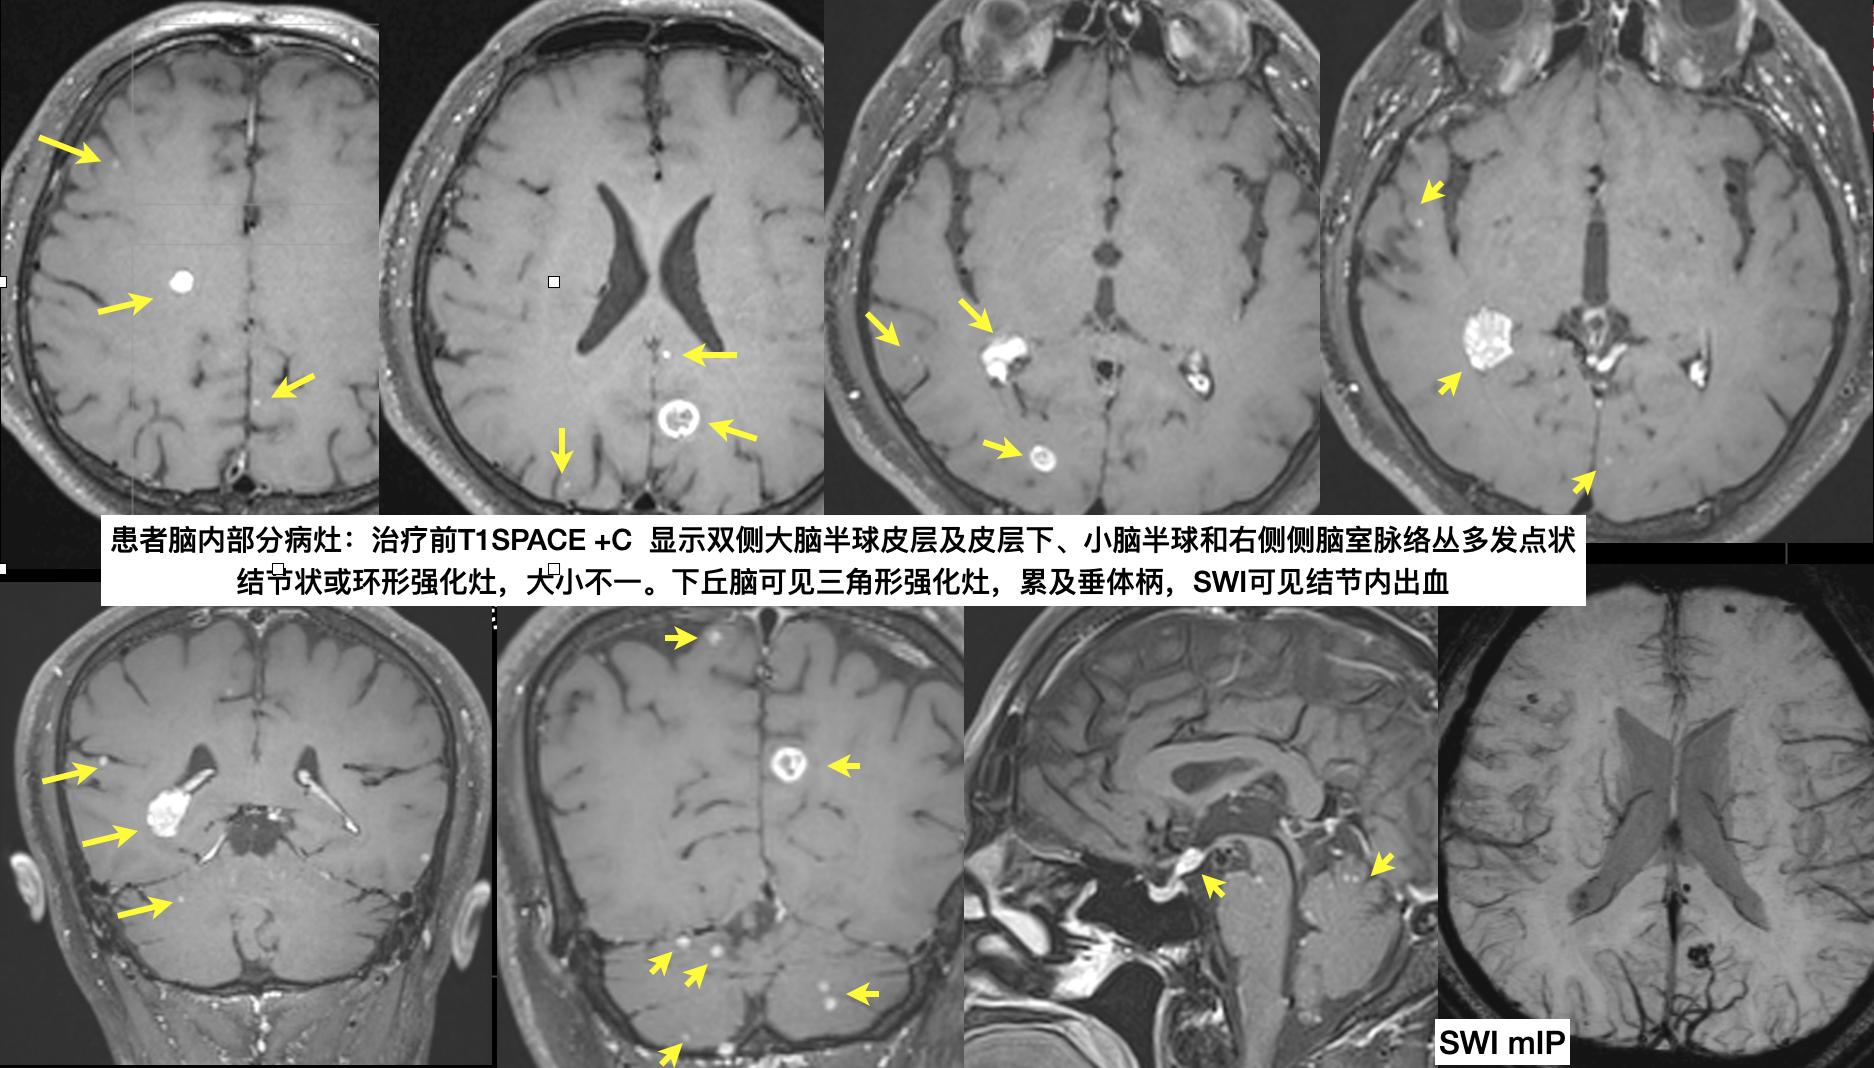

患者王大叔58岁。自觉视物重影多天,伴咳嗽、咳痰、胸闷,遂来我院看门诊,医生给开了头部磁共振平扫检查。恰逢我值班,平扫MRI发现左侧枕叶及右侧脑室脉络丛长T2信号灶伴(SWI)出血,我觉得考虑肿瘤性病变可能,在扫描当时我建议患者进行MRI增强扫描,以进一步明确诊断。

第二天王大叔来找我做完增强扫描完成后,增强图像上可见双侧大脑、小脑可见多发的强化小结节灶,分布以皮层及皮层下为主,最常见的首先是转移瘤,其次脓肿及囊虫病也可以如此,结合病史我认为符合转移瘤表现,建议患者行胸部CT检查排除肺癌脑转移可能。

增强扫描后的MRI图像和病变的典型层面